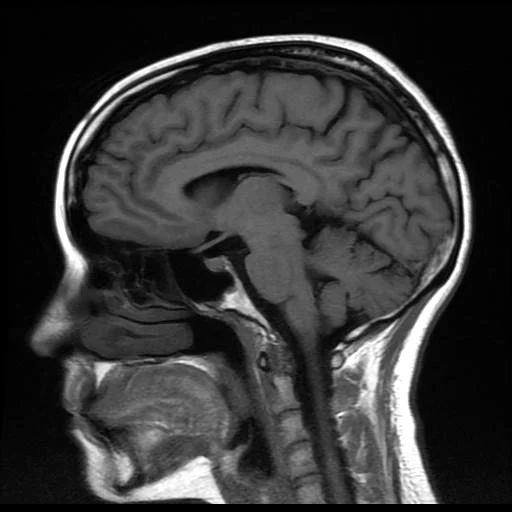

RESONANCIA MAGNÉTICA DE CABEZA

La resonancia de cabeza utiliza campos magnéticos y ondas de radio para generar imágenes detalladas del cerebro y las estructuras circundantes, ofreciendo una visión más completa de los tejidos blandos, como el cerebro, los vasos sanguíneos y los nervios.

La resonancia magnética de cabeza es un procedimiento que permite diagnosticar y evaluar diversas patologías, tales como: infecciones, inflamaciones, tumores, ataque cerebral o convulsión.